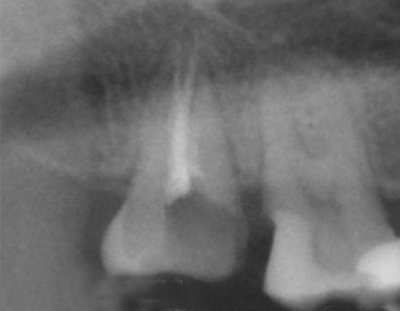

术中X-ray 测试根管长度

术中X-ray 局部放大图